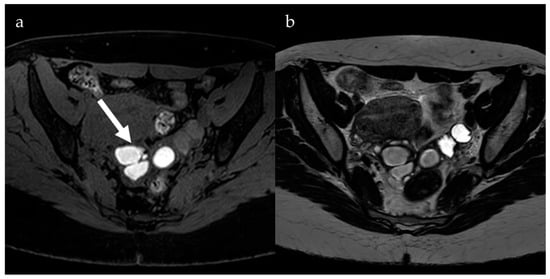

4. Diffusion-Weighted Imaging

- Busard, M.P.H.; Mijatovic, V.; van Kuijk, C.; Bos, I.P.D.; Hompes, P.; van Waesberghe, J. Magnetic resonance imaging in the evaluation of (deep infiltrating) endometriosis: The value of diffusion-weighted imaging. J. Magn. Reson. Imaging 2010, 32, 1003–1009. [Google Scholar] [CrossRef] [PubMed]

- Balaban, M.; Idilman, I.S.; Toprak, H.; Unal, O.; Ipek, A.; Kocakoc, E. The utility of diffusion-weighted magnetic resonance imaging in differentiation of endometriomas from hemorrhagic ovarian cysts. Clin. Imaging 2015, 39, 830–833. [Google Scholar] [CrossRef] [PubMed]